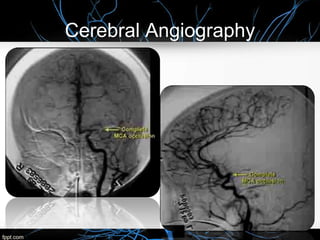

Cerebral Angiography

 Conventional x-ray cerebral angiography is the gold standard for identifying

and quantifying atherosclerotic stenoses of the cerebral arteries and for

identifying and characterizing other pathologies, including aneurysms,

vasospasm, intraluminal thrombi, fibromuscular dysplasia, arteriovenous

fistulae, vasculitis, and collateral channels of blood flow.

 Conventional angiography carries risks of arterial damage, groin hemorrhage,

embolic stroke, and renal failure from contrast nephropathy, so it should be

reserved for situations where less invasive means are inadequate.